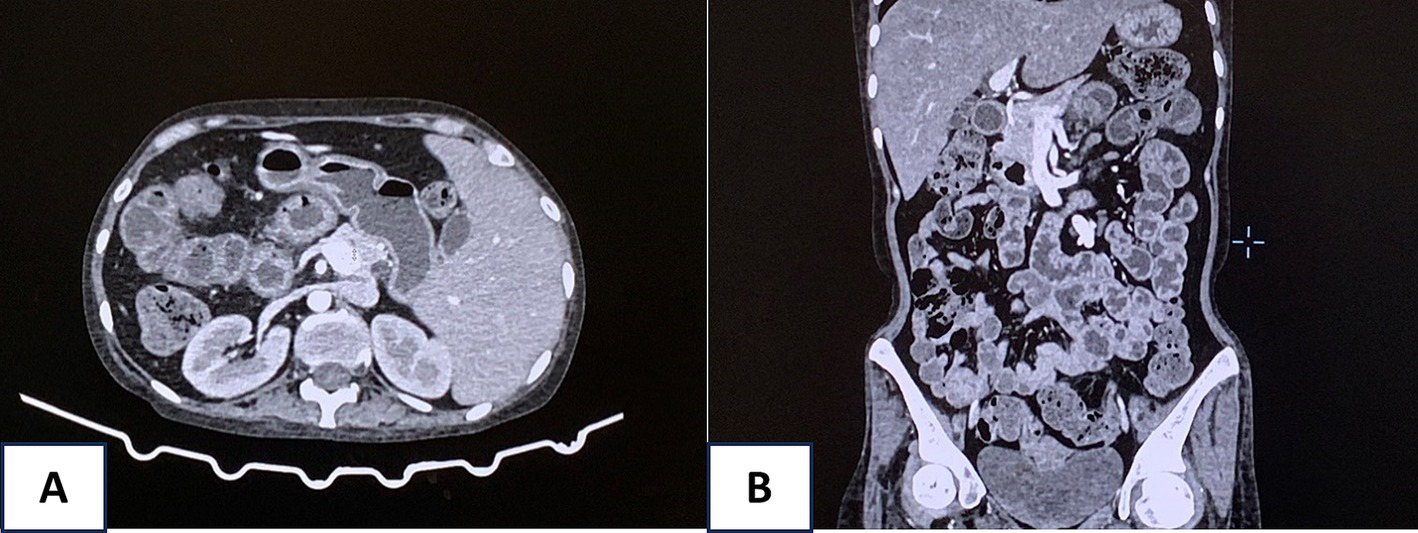

Despite aggressive interventions, the patient’s condition remained unstable, with persistent hematochezia. An abdominal computed tomography (CT) scan revealed edema and a thickening wall throughout the intestinal loops from the duodenum downward, indicating potential bleeding from multiple sites in the digestive tract (Figure 3). Surgical interventions and gastroduodenal embolization were considered but deemed highly risky due to the patient’s critical condition and multiple bleeding locations. After consulting with multiple specialists, a fourth endoscopic examination was performed, revealing active bleeding from duodenal ulcers. The duodenal ulcers were found to be inflamed, edematous, and congested, with a propensity to bleed upon contact. Bleeding control was achieved using clipping and Hemospray. The patient received ivermectin at a dose of 0.2 mg/kg with 9 mg once daily.

Figure 3

Abdominal computed tomography (CT) scan revealed edema and a thickening wall throughout the intestinal loops from the duodenum downward (A, axial view and B, coronal view).